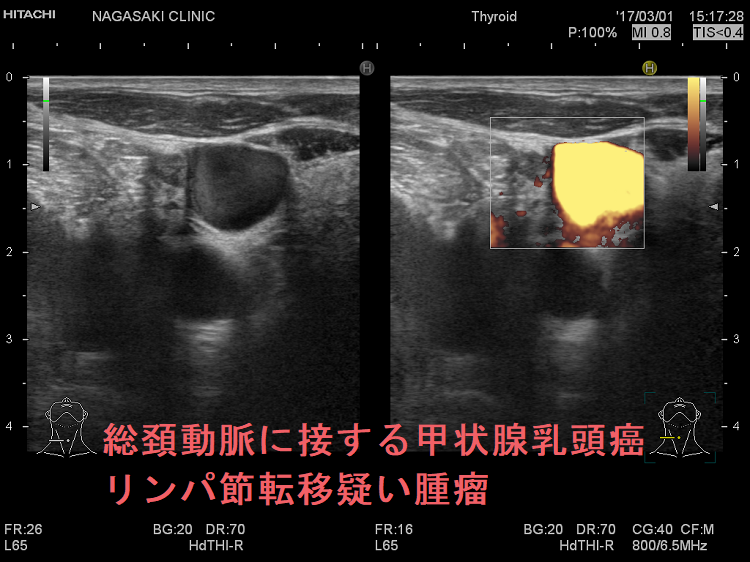

総頚動脈に接する甲状腺乳頭癌リンパ節再発